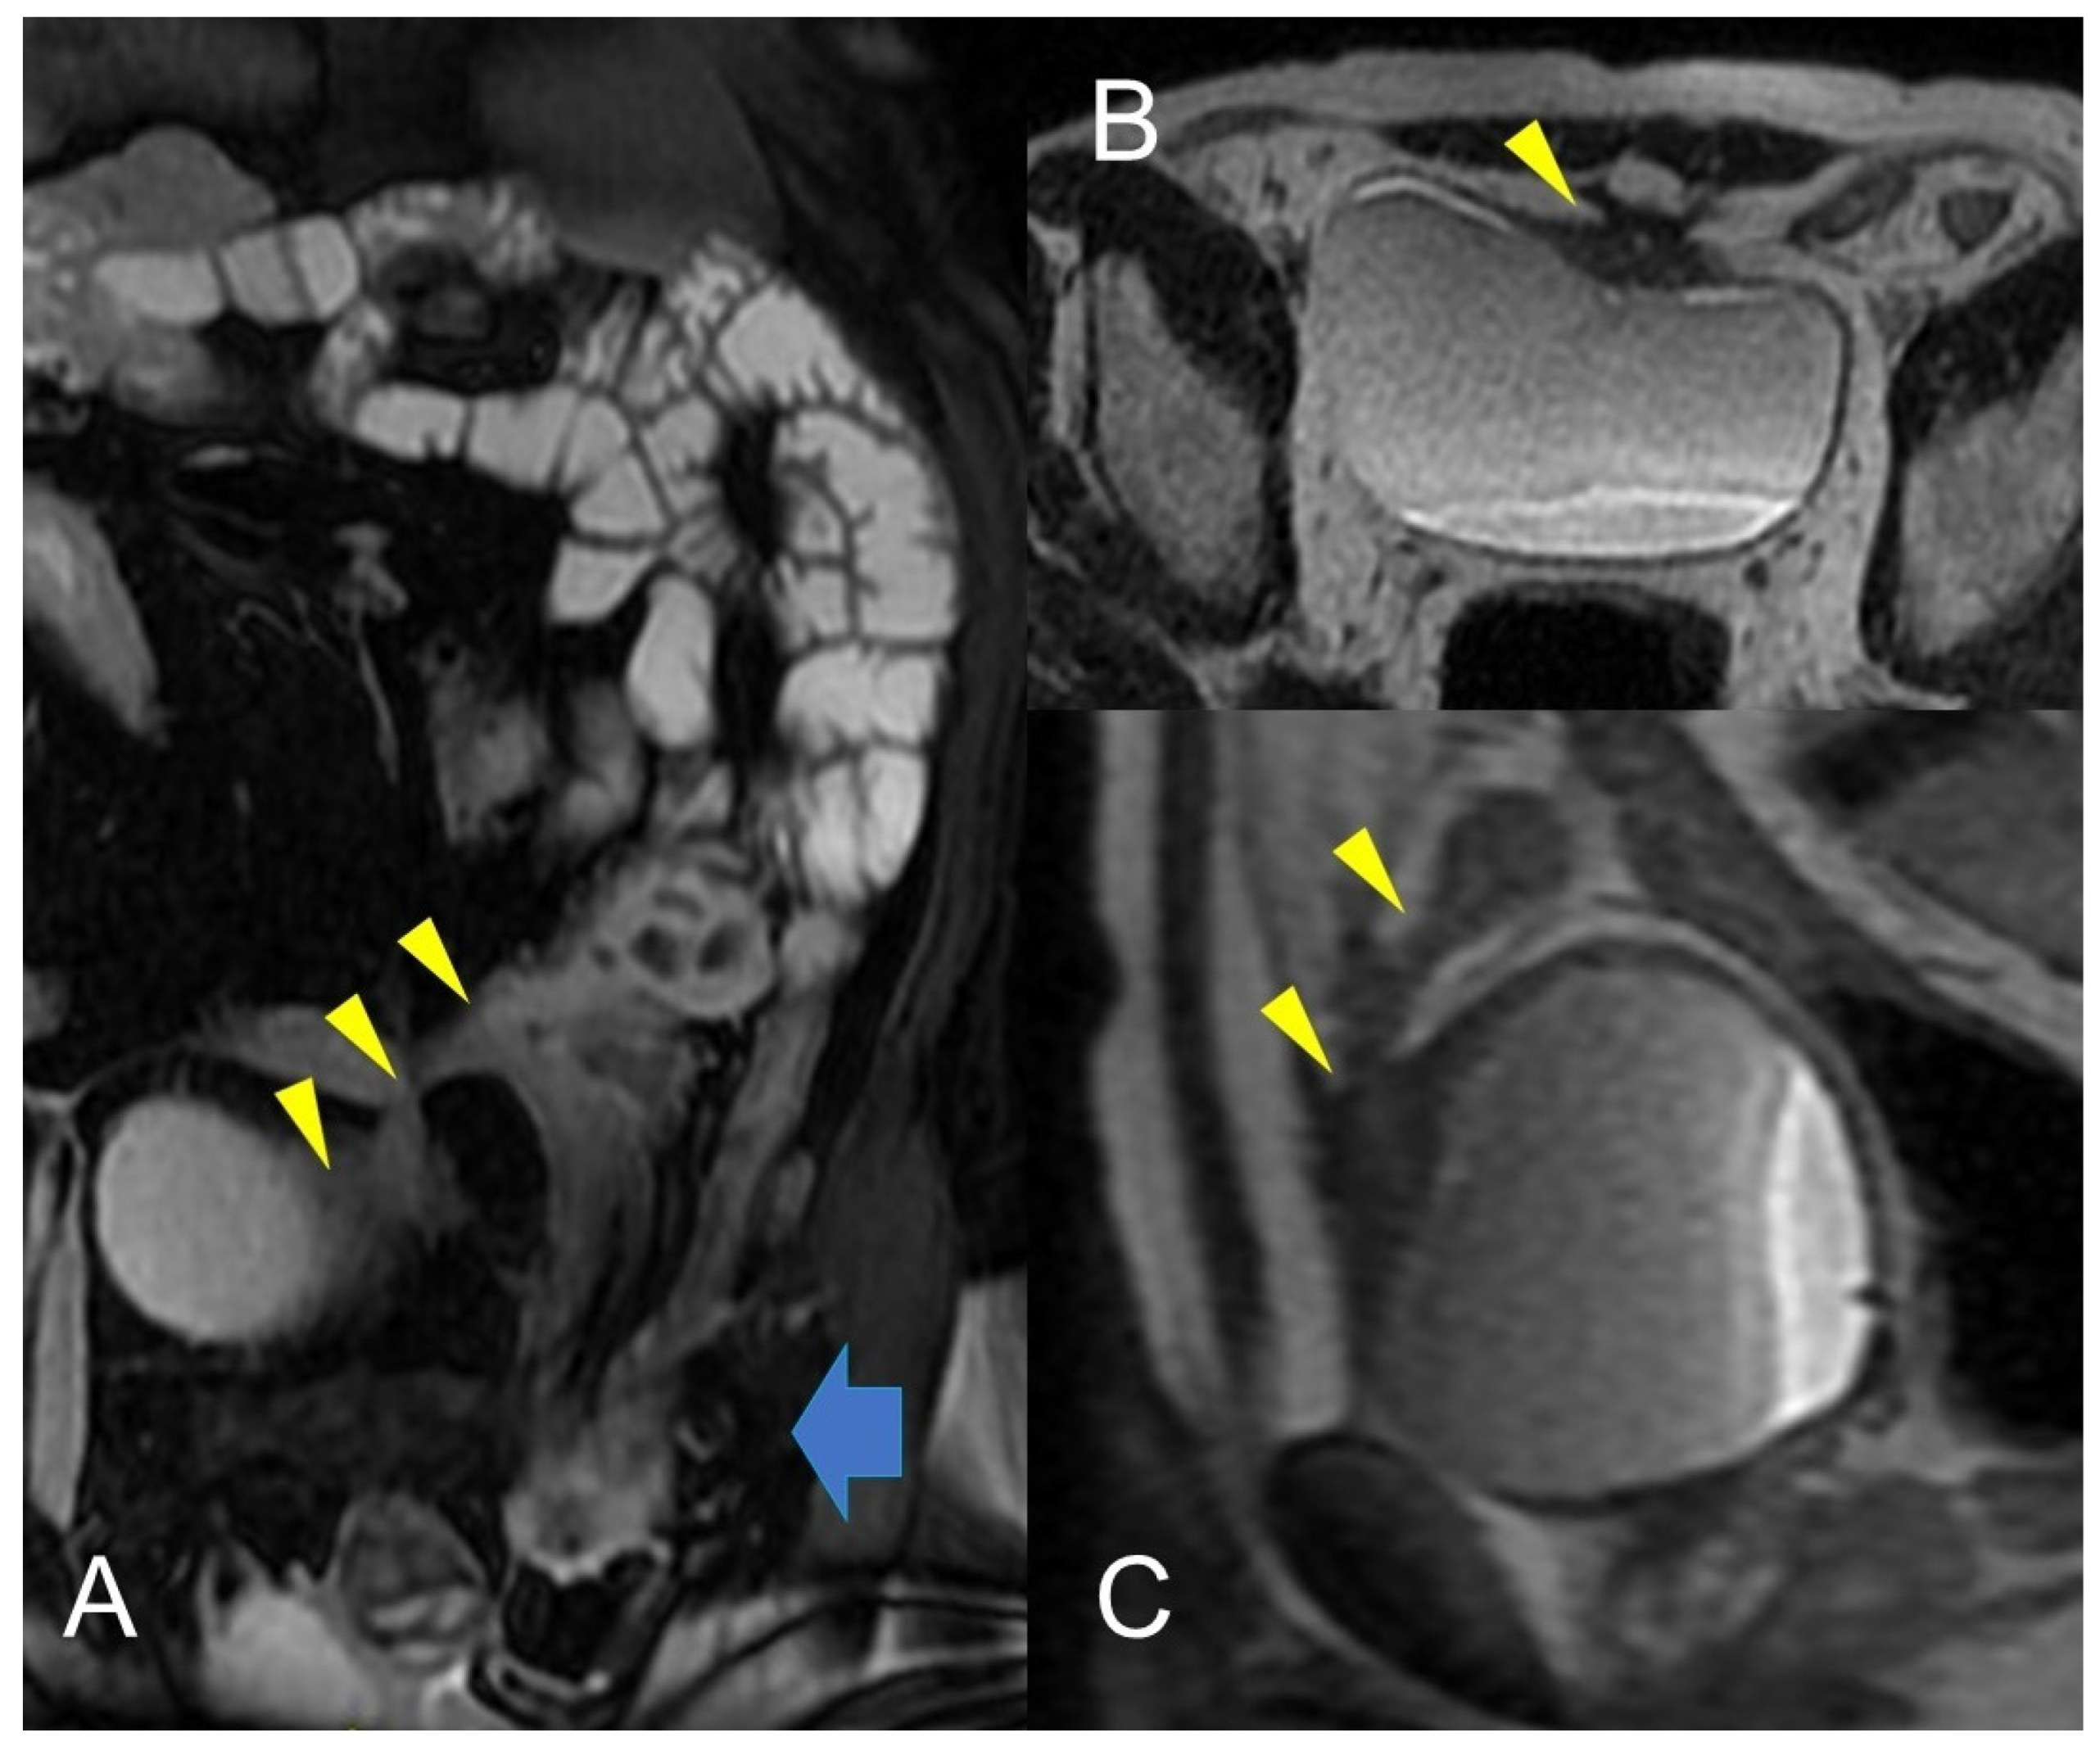

Figure 11.

Crohn’s disease is a common cause of Enterovesical fistula formation. The enterovesical fistula represents an abnormal connection between the enteric lumen and the bladder. Coronal fast imaging employing steady-state acquisition (FIESTA) images (A) show a complex fistula with one arm consisting of an enterovesical fistula (yellow arrowheads). Axial (B) and sagittal (C) T2-weighted MRE image of the same patient shows enterovesical fistula. In (A), inguinal hernia indicated by the blue arrow with involvement of a pathological section of the small intestine.

Unlike the sinus tracts, a fistula is defined as a pathologic channel connecting two or more epithelialized surfaces [11]. Fistulae can be simple (single extra enteric tract: enter enteric, enter colic, enter vesical, enterocutaneous, or rectovaginal) or complex (branching and intersecting fistulas, sometimes with a star-like appearance [5]). They represent a complication in approximately 14–50% of the patients with Crohn’s disease (Figure 9, Figure 10 and Figure 11).